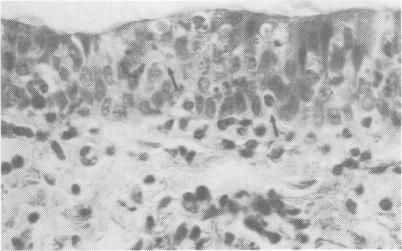

Seven experiments with four calves each were conducted in which the calves spent at least four days of adaptation in an environmental chamber and then were subjected to climatic stress in the form of a number of constant ambient temperature and humidity combinations. On the second day of climatic stress the calves were individually exposed to measured numbers of infectious units of bovine herpesvirus 1 (BHV1, virus of infectious bovine rhinotrachetis) in aerosol. The calves were killed seven or eight days later. Mycoplasma were found in some nasal swabs and in one lung. Certain bacteria but no Pasteurella were often isolated from the lungs. Bovine herpesvirus 1 was isolated from chamber air and from most postinoculation nasal swabs, tracheas and lungs. The number of macro- and microscopic lesions did not appear to be influenced by the climatic conditions of the experiments. The histopathological changes in epithelium at all levels of the respiratory tract were described in detail.

进行了七项实验,每项实验有四头小牛。小牛在环境舱中至少度过四天的适应期,然后经受多种恒定环境温度和湿度组合形式的气候应激。在气候应激的第二天,小牛被单独暴露于经测量数量的牛疱疹病毒1(BHV1,传染性牛鼻气管炎病毒)气溶胶感染单位中。小牛在七或八天后被宰杀。在一些鼻拭子和一个肺中发现了支原体。肺部经常分离出某些细菌,但未分离到巴氏杆菌。从舱内空气以及大多数接种后鼻拭子、气管和肺中分离出了牛疱疹病毒1。大体和微观病变的数量似乎不受实验气候条件的影响。详细描述了呼吸道各级上皮的组织病理学变化。